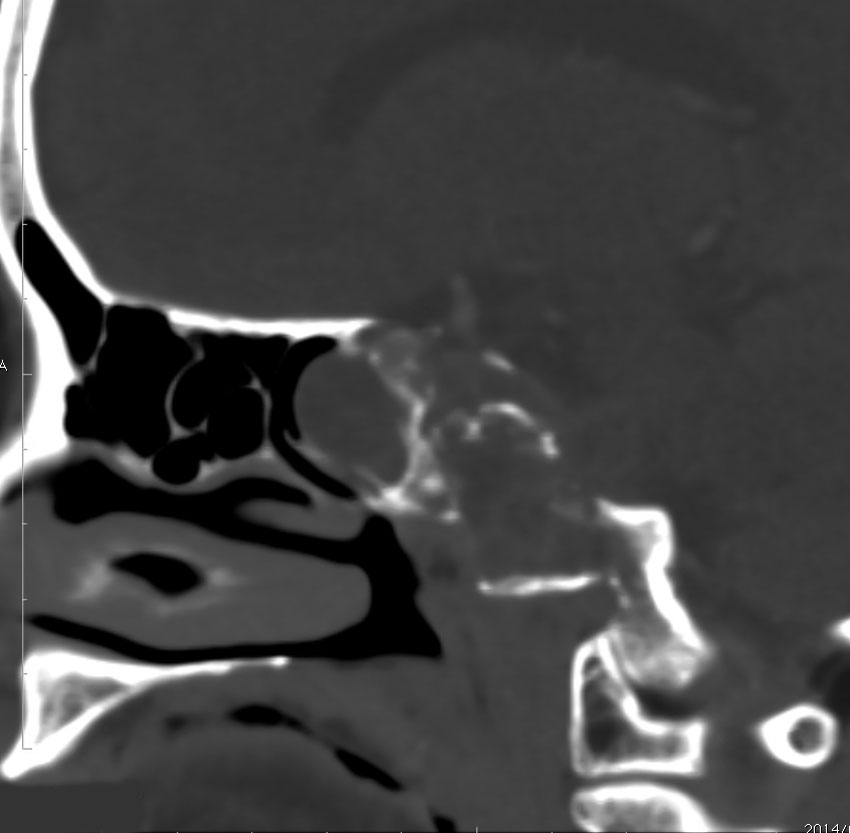

骨軟骨腫が若い時からあって壮年になってから悪性化した軟骨肉腫です。20代のときに右外転神経麻痺が生じて20年以上そのまま経過しました。左のCTでは頭蓋骨の真ん中の斜台というところに異常な骨があって,良性の骨軟骨腫のように見えます。でも右側のMRIでは脳幹部に深く食い込む柔らかい腫瘍の部分が写っていてこれは軟骨肉腫を疑う像です。手術摘出と術後の放射線治療をしました。